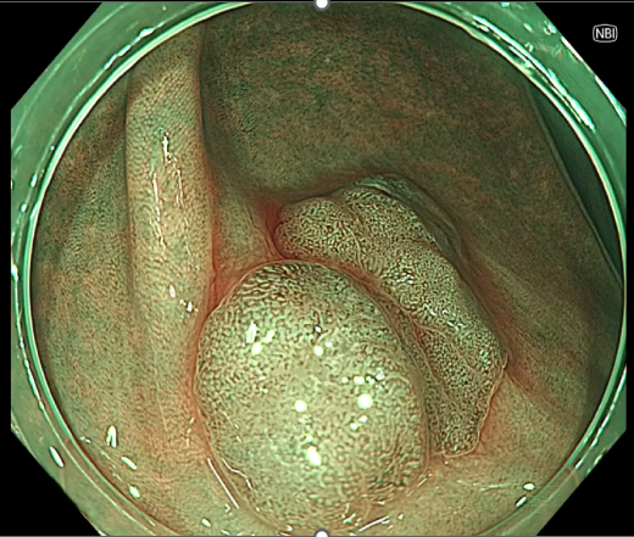

大腸腺腫の画像

NBI(左)よりNBI+TXI(右)では表面構造や血管の視認性が向上している。